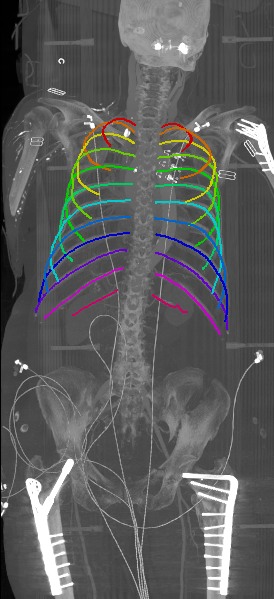

With an average Euclidean distance error of 0.787 mm, we obtained an overall result that is generally better compared to what is reported in the state of the art. Although, it needs to be kept in mind that results are unfortunately not directly comparable as both the data sets as well the evaluation metrics significantly differ across prior work. Similarly to the results obtained on the probability maps, distance errors are significantly higher for first and twelfth rib compared to the rest of the rib cage. As discussed, this is caused by the intrinsic challenges of these ribs, but certainly also an affect of error propagation in that sense that the quality of the probability maps also impacts centerline extraction. Interestingly, the right ribs are generally slightly worse compared to the left ribs, probably due to a slightly unbalanced data set with more challenges on the right side. Figure 5 shows the centerlines which were automatically generated using our walker algorithm from the corresponding network outputs displayed in Figure 4.

Refer to caption

Figure 5: Automatically generated centerline splines associated with the FCNN outputs displayed in Figure 4. The selected case above display common difficulties which are inherent in the data set, such as pads (a) or cables (b), internal devices such as pacemakers (c), stents (d), spinal (e) and femural/humeral implants (f), injected contrast agents (g), patient shape variations such as scoliosis (h), limited field of views (FOVs), i.e. partly missing first (i) or twelfth rib (j).